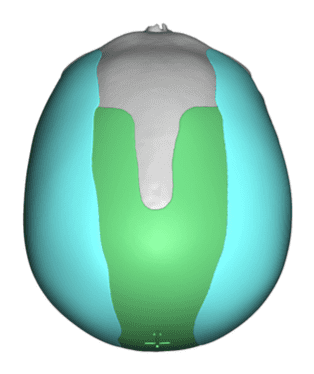

Desire for an improved head shape so that it looks rounder and not so peaked or sloped.

Placement of custom skull implant for parasagittal augmentation to create a rounder head shape. An example of what appears to be a high sagittal crest that is really low parasagittal skull areas.